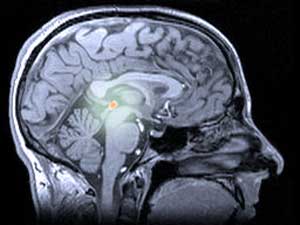

Melatonin, ein Hormon, das von der Zirbeldrüse im Gehirn produziert wird, ist in Pillenform erhältlich und wird zur Behandlung von Schlafstörungen eingesetzt. Neue Forschungsergebnisse deuten darauf hin, dass es die Huntington-Krankheit bei Modellmäusen verlangsamen kann – eine großartige Nachricht, aber es bedeutet nicht, dass jeder es sofort einnehmen sollte.

Beim Menschen und anderen Tieren wird Melatonin von der Zirbeldrüse (ausgesprochen ‚pie-kneel‘) produziert, einer leicht mysteriösen Struktur tief im Gehirn. Die Zirbeldrüse wird manchmal als „drittes Auge“ bezeichnet, weil sie bei einigen Eidechsen auf dem Kopf sitzt und dazu dient, die Schatten fliegender Raubtiere zu erkennen.

Licht und Dunkelheit sind auch wichtig für die menschliche Zirbeldrüse und das von ihr produzierte Melatonin. Die Zirbeldrüse empfängt Lichtsignale von den Augen und setzt Melatonin frei, wenn es dunkel ist. Das Melatonin wirkt auf die Schlafzentren des Gehirns und macht uns schläfrig. Langfristig reguliert der tägliche Abfall und nächtliche Anstieg des Melatonins unser Schlaf-Wach-Muster und hält es im Einklang mit den Veränderungen des Tageslichts.